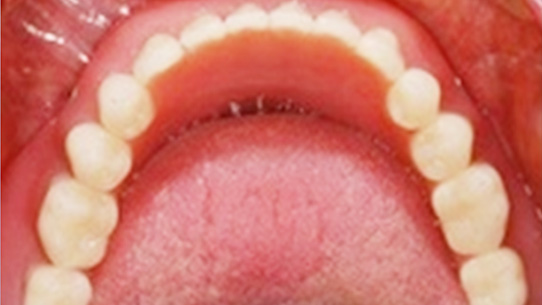

틀니가 번번히 탈락되어 일상생활이 불편하셔서 내원, 고정력이 없는 틀니를 사용하여 잇몸 염증과 통증 있으셨습니다. 상악의 경우 틀니를 오랫동안 착용하여 잇몸 뼈 소실이 심해 일반 틀니를 제작하고, 하악의 경우 임플란트 2개를 식립 후 임플란트 틀니를 제작해 드렸습니다.

자석으로 연결장치를 사용해 틀니를 갈아 끼우기 때문에 빠질 염려가 적다.